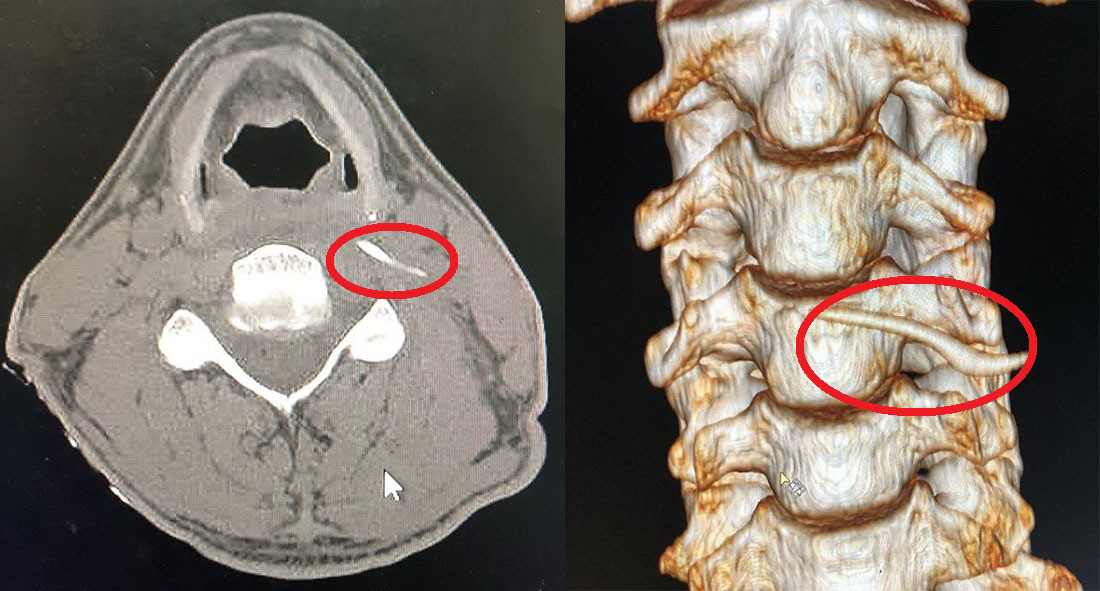

| Hình ảnh cắt lớp vi tính và Xquang xương cá trong cổ anh Nam |

Tại khoa Tai Mũi Họng, BV Hữu nghị Đa khoa Nghệ An, anh Nam được các bác sĩ cho đi chụp cắt lớp vi tính và X-quang.

Hình ảnh cho thấy, chiếc xương sắc nhọn dài gần 4 cm đâm sâu vào vị trí thành sau hầu thanh quản, nằm trong khoang cạnh hầu và ngang mức bờ trên sụn giáp, sát cột sống cổ và miệng thực quản.

Nhưng với bệnh nhân Nam, chiếc xương quá sắc nhọn đã đâm sâu, không để lại vết tích rõ ràng. Dù hình ảnh cận lâm sàng xác định vị trí cơ bản, nhưng thực tế để tìm được chính xác lại là câu chuyện phức tạp.